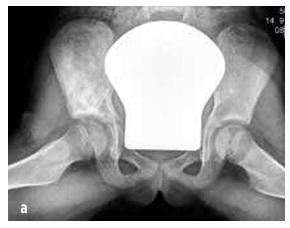

A szeptikus ízületi gyulladás 50% -ban két éves korig jelentkezik, és 75% -ban az alsó végtagok ízületeit érinti (térd > csípő > boka) (lásd a 4. ábrát). Az osteomyelitis leggyakrabban a metafízisben lokalizálódik.

Csont- vagy ízületi fertőzésre gondolunk olyan gyermekeknél, akiknél hirtelen jelentkeznek a következő tünetek: láz, megmagyarázhatatlan sántítás és/vagy abnormális végtag tartás, a végtag használatának megtagadása, mozgáskorlátozottság, izom-csontrendszeri fájdalom ± helyi tapintási fájdalom az ízületben vagy csontban, valamint duzzanat és bőrpír (lásd a 4. ábrát). CAVE: a kisgyermekek pontatlanul lokalizálják a fájdalmat (pl. a csípőből a térd területére áthelyeződő fájdalom).

4. ábra

Klinikai lelet szeptikus ízületi gyulladás esetén